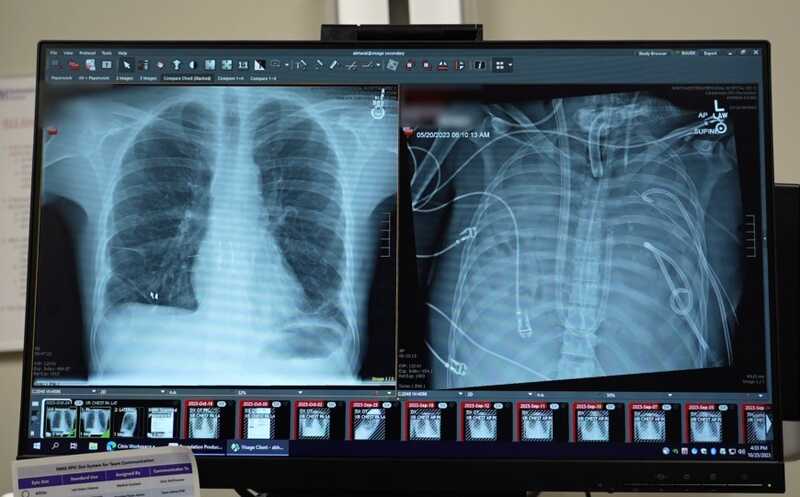

Новые легкие пациента (слева) и легкие до пересадки, после ОРДС, вызванного гриппом и бактериальной пневмонией (справа)

Credit:

Northwestern Medicine | Пресс-релиз